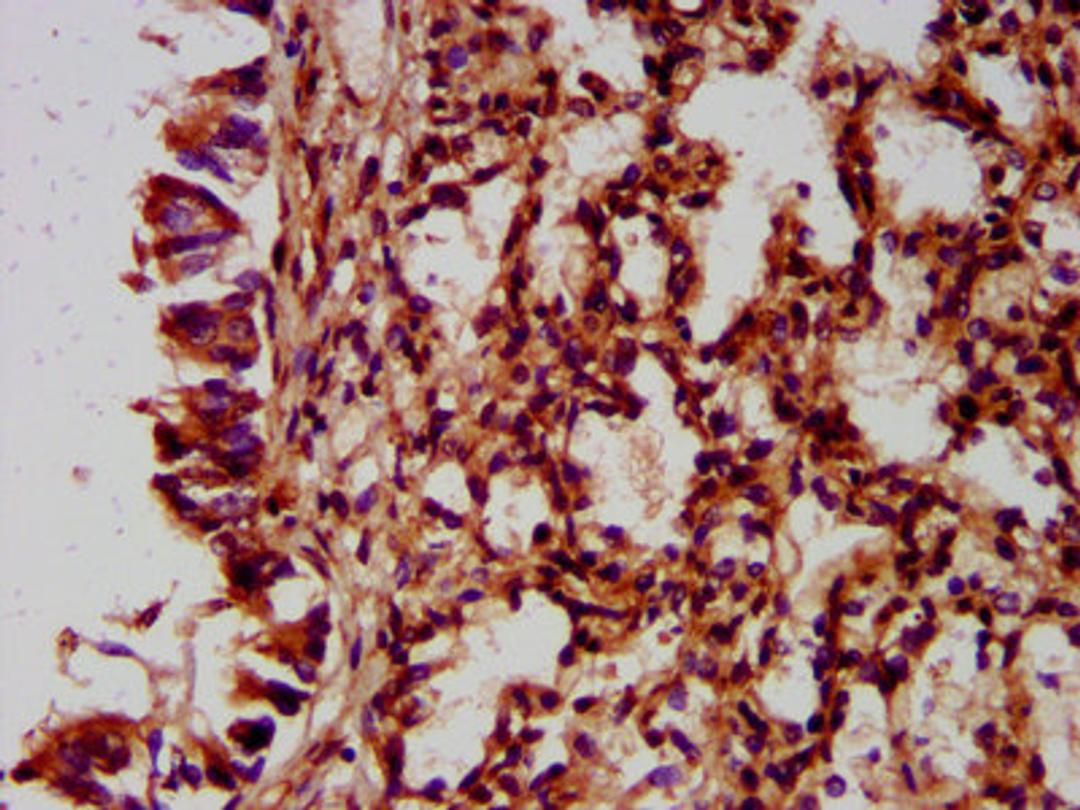

IHC image of CSB-PA771457LA01HU diluted at 1:400 and staining in paraffin-embedded human lung tissue performed on a Leica BondTM system. After dewaxing and hydration, antigen retrieval was mediated by high pressure in a citrate buffer (pH 6.0). Section was blocked with 10% normal goat serum 30min at RT. Then primary antibody (1% BSA) was incubated at 4°C overnight. The primary is detected by a biotinylated secondary antibody and visualized using an HRP conjugated SP system.